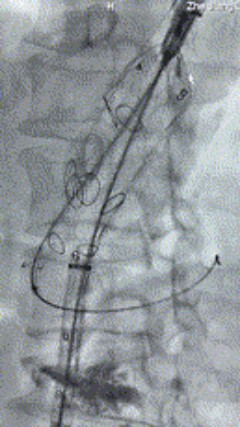

5. 撤出腹腔干导丝导管,经左肱动脉长鞘继续抓捕预置导丝将长鞘超选至另一侧内分支,后超选进肠系膜上动脉,沿导丝送入九州ku酷游覆膜支架10*100mm一枚,近端重叠内分支,远端重叠于肠系膜上动脉,并予以10mm球囊后扩,手推造影显影良好。

6. 解除束径,打开近端后释放,经肱动脉长鞘超选支架外分支,并进一步超选右侧肾动脉,交换加硬导丝,送入覆膜支架6*50mm和7*60mm各一枚,并予以球囊后扩张,手推造影显影良好。

7. 经长鞘重新选入左侧外分支,并超选进左肾动脉,沿导丝送入外周血管覆膜支架7*60mm一枚,并予以球囊后扩张,手推造影显影良好。